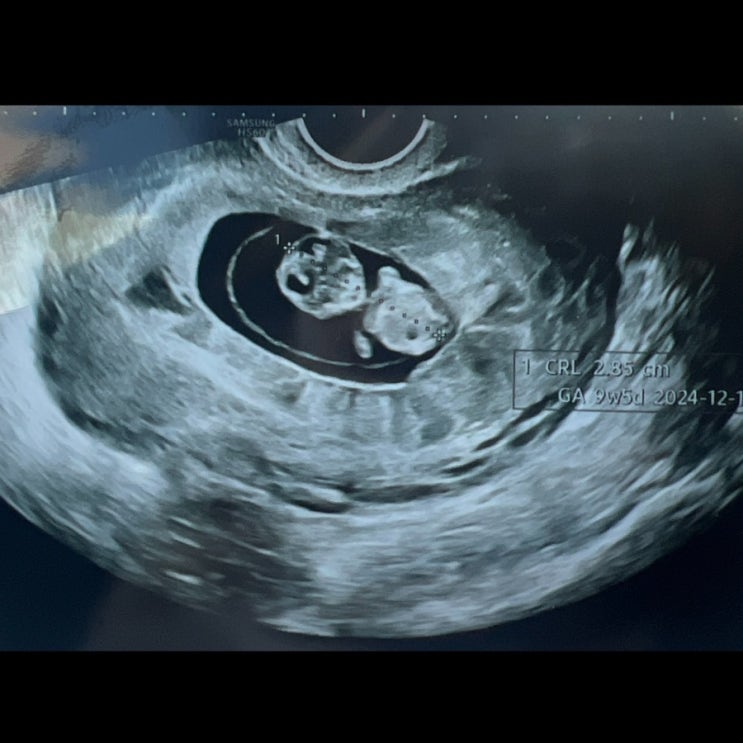

다낭성 난소 증후군 임신 기록 #13 임신 9주차 피비침 피고임 입원

다낭성 난소 증후군 임신기록 13 9주차 피고임 피비침 입원 9~11주차 기록❤️ 9주차에 들어오고 회사에서 ...